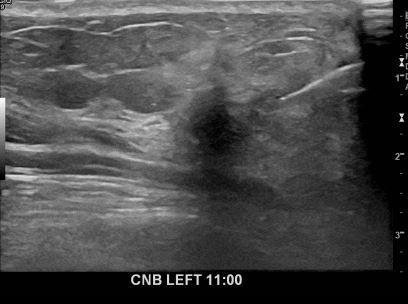

아산유외과개원후649번째 유방암진단

상기환자 외부검사상 이상소견으로 내원하신 60대여성으로 좌측유방의 의심스러혹

조직검사시행해 유방암 진단되었습니다.